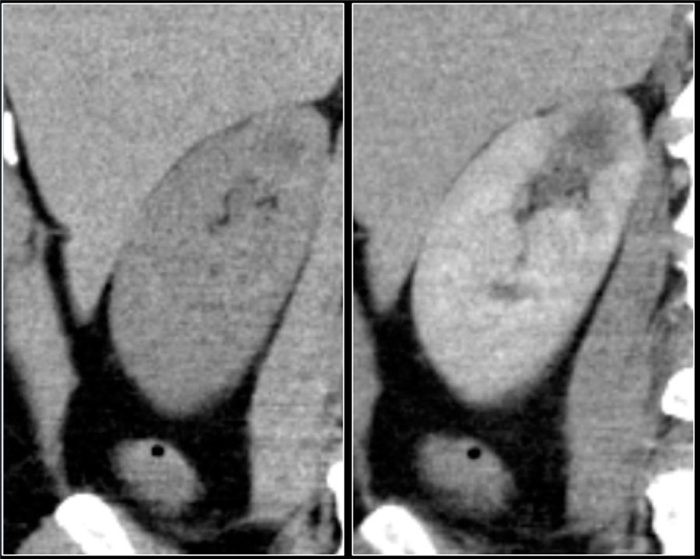

(Слева) КТ правой почки с контрастированием, аксиальная проекция: выявлено крупное образование в почке, не накапливающее контраст и окруженное капсулой с плотностью 20 HU (предположительно абсцесс).

(Справа) УЗИ правой почки в сагиттальной плоскости: у того же пациента выявлено округлое анэхогенное образование с низкоуровневыми внутренними эхо-сигналами и задним акустическим усилением. Лихорадка в анамнезе и данные визуализации указывают на наличие абсцесса.